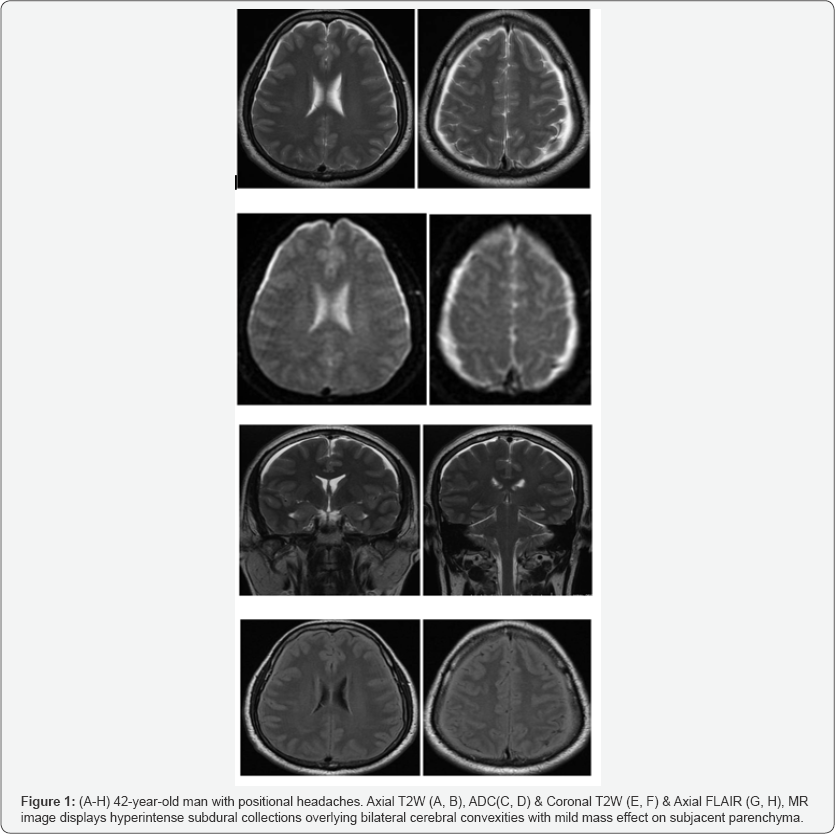

CT brain study was unremarkable and the patient proceeded fluid collections (Figure 1A-1F), which were located in the to Non contrast & contrast-enhanced MRI. On T2-weighted cerebral and cerebellar subdural spaces and were also hyper images, there were, bilaterally symmetrical small hyper intense intense on FLAIR images (Figure 1G & 1H).

Various imaging techniques help to diagnose SIH and guide treatment. MRI of the brain and spine identify signs of SIH. The common qualitative MRI findings in SIH represent the sum of loss of CSF volume and compensatory changes in response to the leakage. Thin, bilateral, subdural fluid accumulation over the cerebral and cerebellar convexities is commonly seen in about 50% of patients [20-22]. The pachymeningeal (dural) enhancement is bilateral, diffuse, involves both supratentorial and infratentorial compartments and spares the leptomeninges [7]. This common (in 80% of cases) and striking appearance has been likened to a “felt tip pen” outlining the thickened, enhancing dura in a diffuse and non-nodular pattern [23]. It is thought to be caused by engorgement of the small, thin-walled dilated blood vessels in the subdural zone [5].